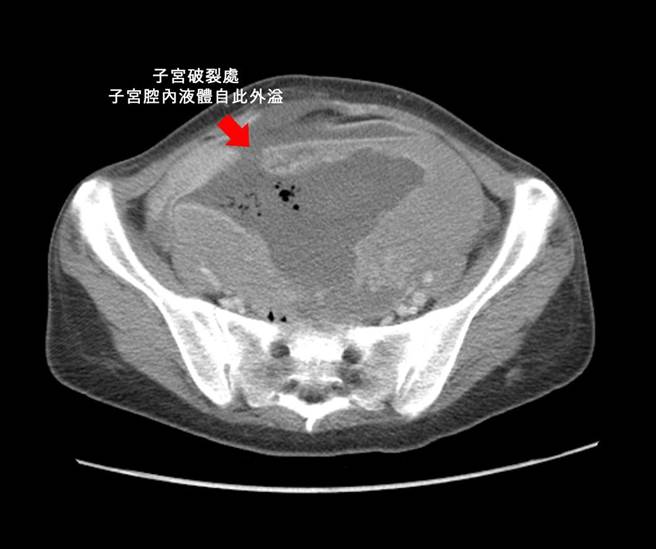

黄兆麒指妇人到院时,妇人到院时血液检查血红素已掉到2.7(正常为12以上),再紧急做电脑断层检查,赫然发现她的子宫肌瘤有17公分之大,且已经有子宫破裂的迹象,经紧急开刀摘除子宫,同时发现因腹壁筋膜受损,形成腹壁疝气,必须二次手术修补筋膜层,也就是经两次手术才让该妇女保住生命。